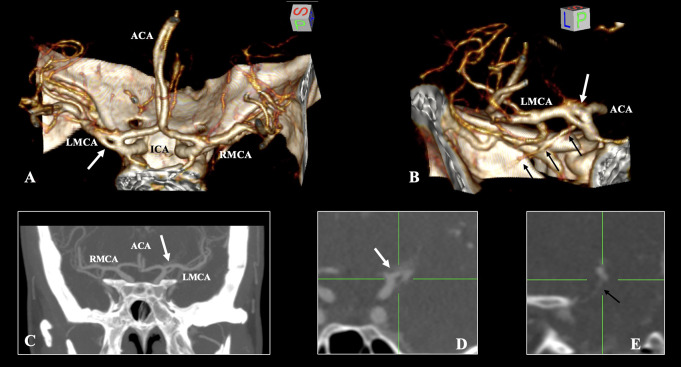

The cerebral arterial circle exhibits considerable morphological variability. Variations in the middle cerebral artery (MCA) are infrequent occurrences that can be readily identified via imaging techniques. The current imaging report describes a rare variant of the MCA consisting of a duplicate origin, which was incidentally discovered in a 42-year-old female patient through computed tomography angiography. The duplicated origin of the MCA was identified on the left side of the cerebral arterial circle, forming an arterial ring with the temporopolar branch of the MCA originating from one of its limbs. The remainder of the arterial circle demonstrated no variants. It is essential to distinguish variants of the MCA without conflating them. The present variant is accurately characterized as a 'duplicate origin", it should not be confused with fenestrations, and has a reported prevalence of 0.1%. Comprehending such arterial variations is vital prior to undertaking endovascular or neurosurgical procedures in the region.